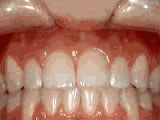

Missing lateral incisors

This patient's lateral incisors were congenitally missing. She had braces for 20 months to move the teeth into their correct positions, then the missing teeth were replaced with bonded "Maryland" bridges.